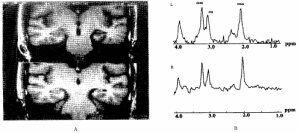

1.常規EEG、視頻EEG和動態EEG監測可顯示尖波、棘波、尖-慢波、棘-慢波等癇性波型,有助於癲癇發作和癲癇狀態的確診。

4.必要時可行頭部CT和MRI檢查。